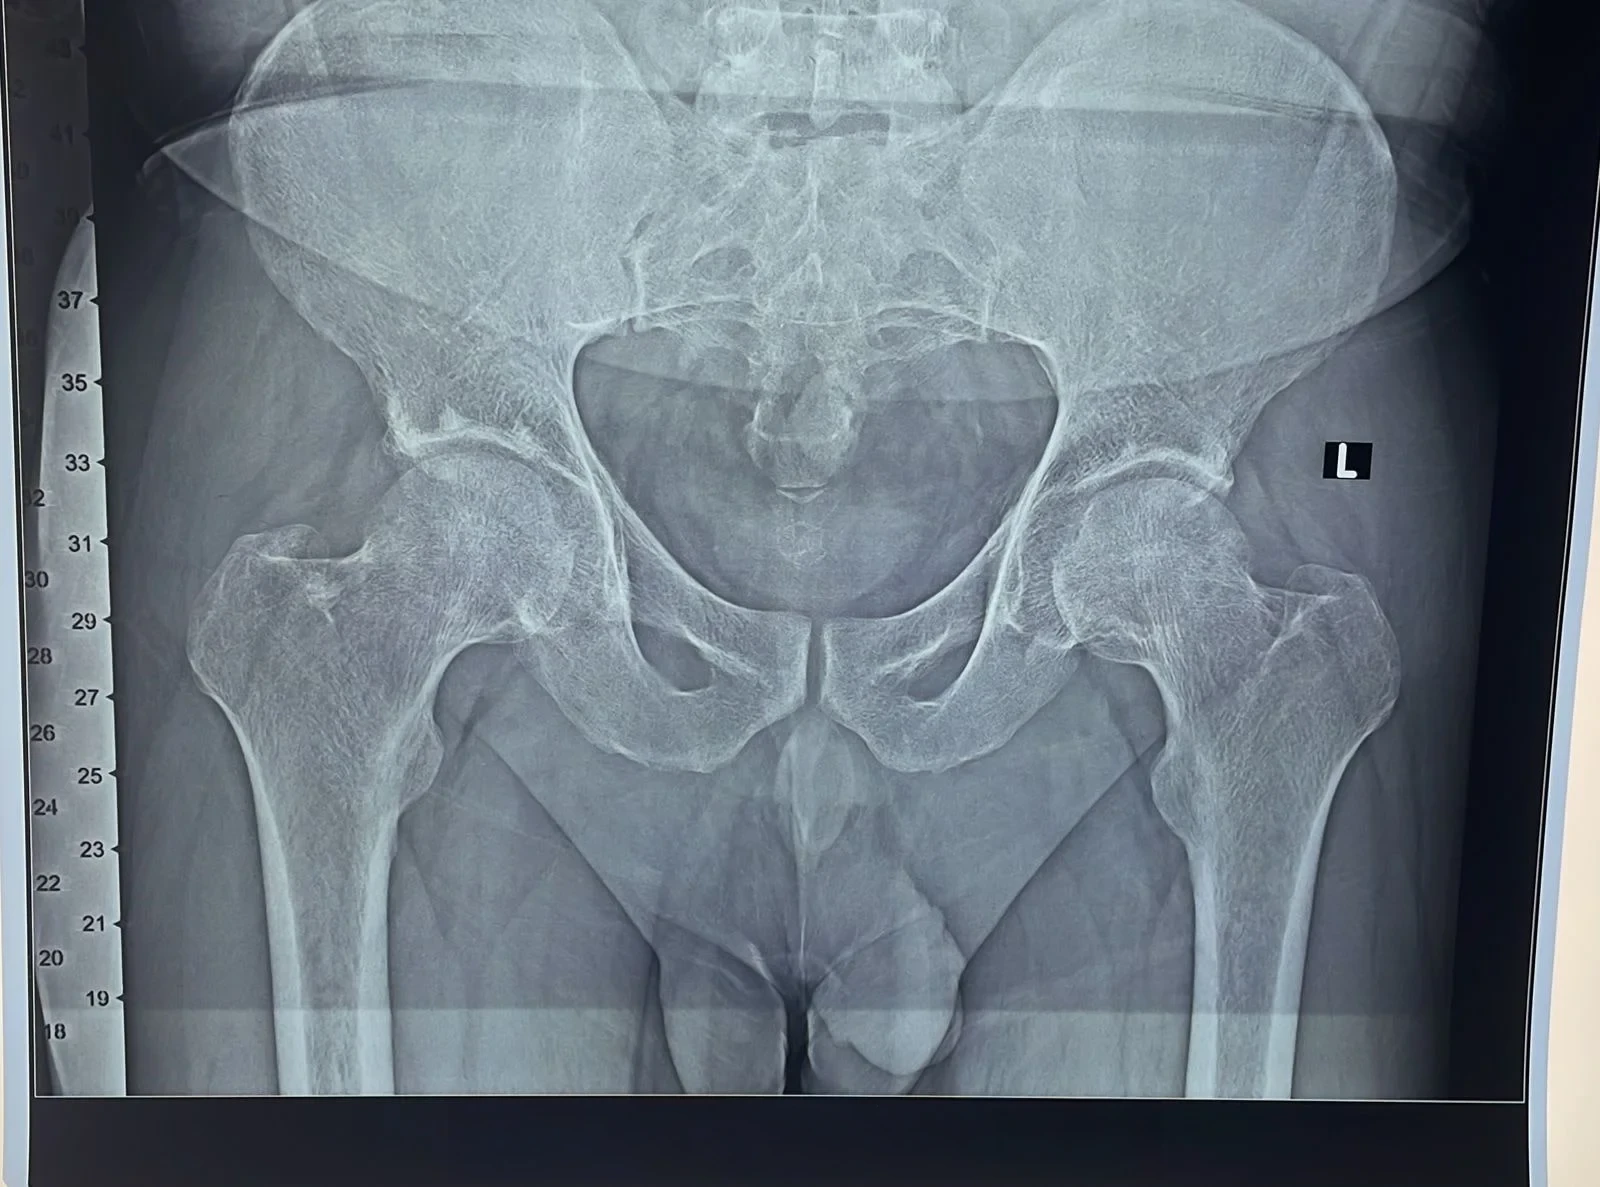

Digital X-Ray Pelvis with Both Hip Joint: True Size AP View

Digital X-Ray Hip Joint: Lat View

Digital X-Ray: Femur Whole Length with Knee Joint (AP/Lat view)

III. Pre-Op Templating :

Pre-Operative estimation of probable implant sizes, Offset & LLD